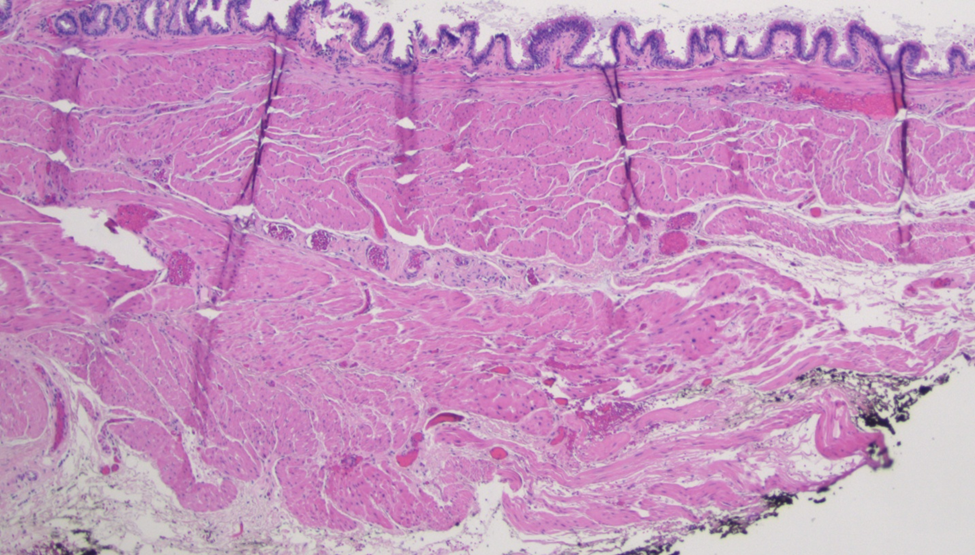

A 28-year-old healthy gentleman with no prior medical history presented to the emergency room with sudden onset of severe right upper quadrant and epigastric abdominal pain associated with nausea and vomiting. Liver enzymes and lipase were normal. CBC showed mild leukocytosis (12.24 K/microL).  Cross-sectional imaging revealed a well-circumscribed soft density lesion adjacent to the gastroesophageal junction (Fig. 1). Ultrasound evaluation did not show any cholecystitis or gall stones. Esophagogastrostomy did not show significant changes in the esophagus or in the gastroesophageal junction or in the stomach. Endoscopic ultrasound evaluation showed a well encapsulated lesion measuring 3 cm not arising from the muscularis propria of the esophagus but close to the GE junction with both liquid and solid contents (Fig. 2). Needle aspiration showed mucinous material suggesting possible esophageal duplication cyst.  Laparoscopy was performed ,revealing a pedunculated  cystic lesion at the gastroesophageal junction (Fig. 3). It was stapled at its origin, with a bougie in the esophagus to minimize the risk of narrowing the esophageal lumen (Fig. 3). Histopathological examination confirmed it was indeed an esophageal duplication cyst (Fig. 4,5 &6). The inner lining of the cyst was ciliated columnar epithelium (Fig. 4). Interestingly double layer of smooth muscle was noted (Fig. 6). Following surgical removal, the pain completely resolved and on follow up the patient was feeling completely normal.

Fig. 5. Low Power view (4x) of an H&E stained section of showing cystic structure with a well-developed smooth muscle layer forming the wall and lined by ciliated columnar epithelium. No cartilage identified.

Fig. 6. Another low power view (4x) of an H&E stained section of the esophageal duplication cyst demonstrating well-developed double smooth muscle layer.